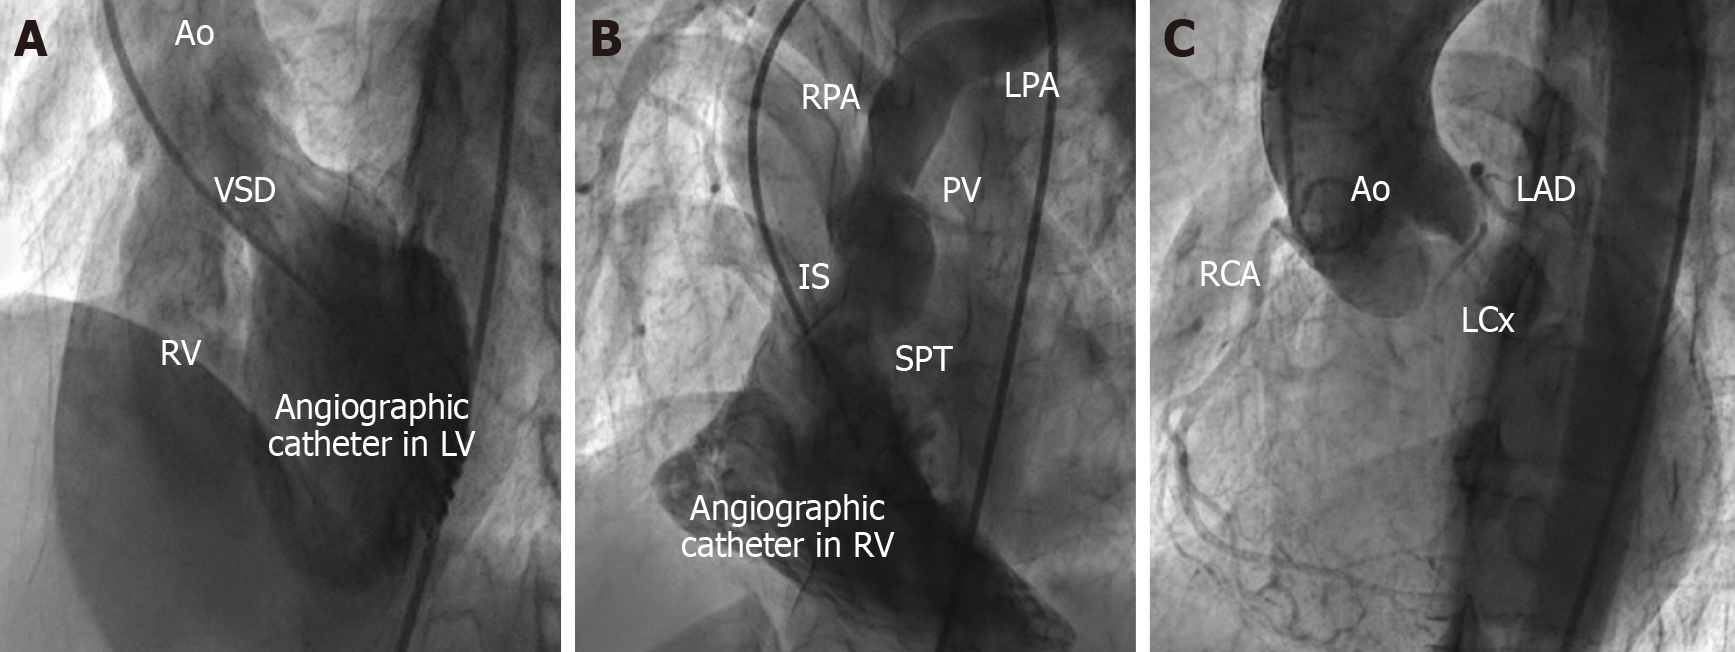

Invasive catheter angiography has gradually been supplanted by newer, non-invasive imaging modalities such as CT and CMRI. However, certain situations warrant angiography as a part of pre-operative evaluation. For example, to clearly visualize the stenosis in an adult patient of TOF with poor echo windows and unclear morphology of RVOT obstruction in imaging, for accurate assessment of the size and location of VSDs in the presence of multiple muscular VSDs, in TOF with pulmonary atresia, to assess the adequacy of comparison between native PA supply to lungs and aortopulmonary collateral supply (Figure 10). These are a few situations where catheter-based angiography is preferred for pre-surgical planning. Apart from diagnostic purposes, invasive procedures like RVOT stenting, PDA stenting, coiling of MAPCAs, balloon pulmonary valvuloplasty, etc., can also be performed in a case of TOF with uncontrolled spells[51,52].

Figure 10

Figure 10  Catheter angiography images in a patient with tetralogy of Fallot. A: Left ventricle angiography showing large ventricular septal defect, aortic override; B: Right ventricle angiography showing multilevel stenosis at sub-valvar, valvar, supra-valvar region; C: Aortic root angiography showing origin of coronaries. Ao: Aorta; VSD: Ventricular septal defect; RV: Right ventricle; LV: Left ventricle; RPA: Right pulmonary artery; LPA: Left pulmonary artery; PV: Pulmonary valve; IS: Infundibular septum; SPT: Septoparietal trabeculations; RCA: Right coronary artery; LCx: Left circumflex artery; LAD: Left anterior descending artery.